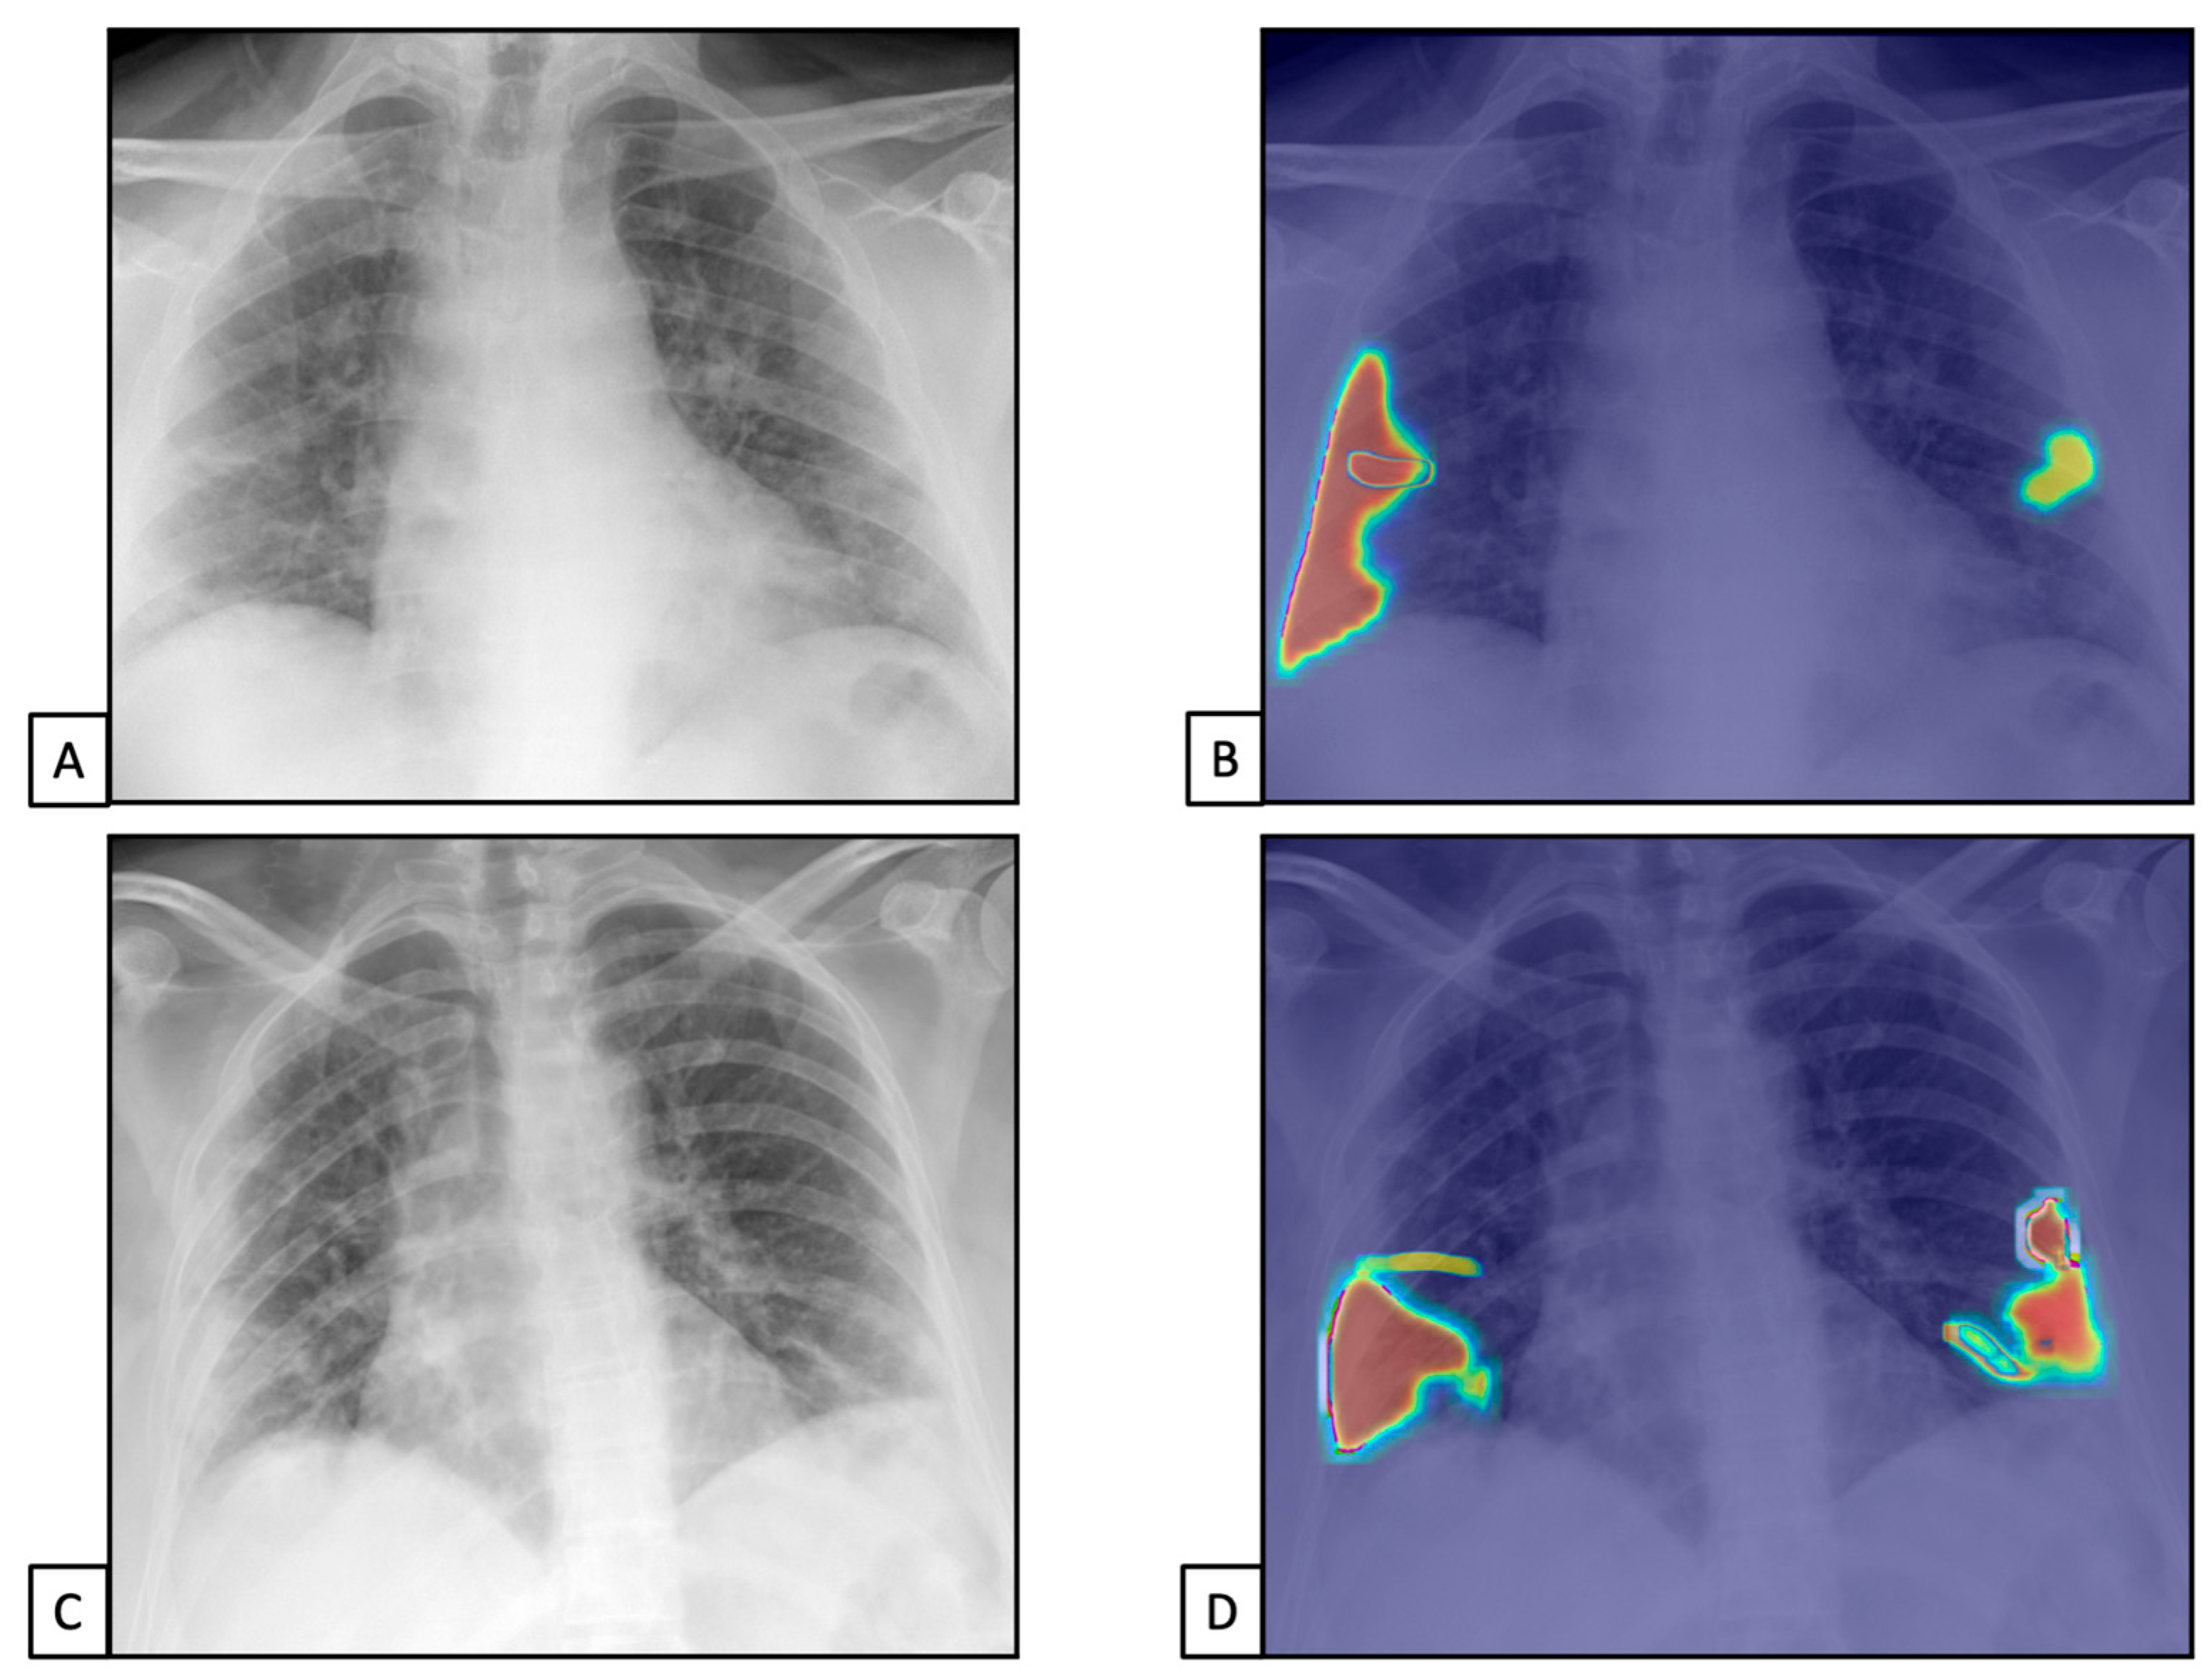

The TPs and TNs, according to the radiologist, were similar to the AI system ones [n = 1450 (67.8) and n = 503 (23.5), and n = 1419 (66.3) and n = 515 (24.1), respectively]. Similar results were found for FPs and FNs [n = 127 (5.9), n = 60 (2.8), n = 127 (5.9), and n = 79 (3.7), respectively]. This resulted in 96% sensitivity (95%CIs = 94.9–96.9) and 79.8% specificity (76.4–82.9) for the radiologist and 94.7% sensitivity (93.4–95.8) and 80.2% specificity (76.9–83.2) for the AI system (Figure 3). The radiologist showed 91.9% PPV (90.7–93.0) and 89.3% NPV (86.7–91.5), while the AI system showed 91.7% PPV (90.5–92.8) and 86.7% NPV (83.9–89.0).

Figure 3.

Chest X-rays of patients admitted to the emergency department with the suspicion of COVID-19 infection belonged to dataset 1. (A,C) represent CXRs acquired at the bedside, showing multiple slight interstitial and alveolar opacities located peripherally and with a lower distribution. (B,D) The AI system analysis obtained in a few seconds displays the pathological zones. The AI system reported a high suspicion of COVID-19 infection (99.99%). The final diagnosis was lung involvement by COVID-19 pneumonia.

The TPs and TNs, according to the radiologist, were similar to the AI system ones [n = 1218 (81.2) and n = 235 (15.6), and n = 1191 (79.4) and n = 234 (15.6), respectively], both with similar FPs and FNs [n= 127 (5.9) for both, and n = 60 (2.8) and n = 79 (3.7), respectively]. This resulted in 97.9% sensitivity (98.0–99.3) and 88% specificity (83.5–91.7) for the radiologist and 97.5% sensitivity (96.5–98.3) and 83.9% specificity (79.0–87.9) for the AI system (Figure 4 and Figure 5).

3.4. Diagnostic Accuracy of AI System

The confusion matrix showed a precision of 97.1% for COVID+, with a recall of 90.1% and a f1-score of 93.7%. Analogous results were found for pneumonia+ patients with 94.8% precision, 95.4% recall, and 95.1% f1-score. Also, in cases of healthy subjects, we found 90.1% precision, 96.8% recall, and 93.3% f1-score. Finally, the AI system reached an accuracy of 93.8%, with a misclassification rate of 6.2% and 93.8% weighted-F1.

The confusion matrix is reported in Figure 6.

Figure 6.

Confusion matrix for the AI system. Data included in the green squares represent correctly labeled CXRs. Data contained in the red squares represent incorrectly labelled CXRs.